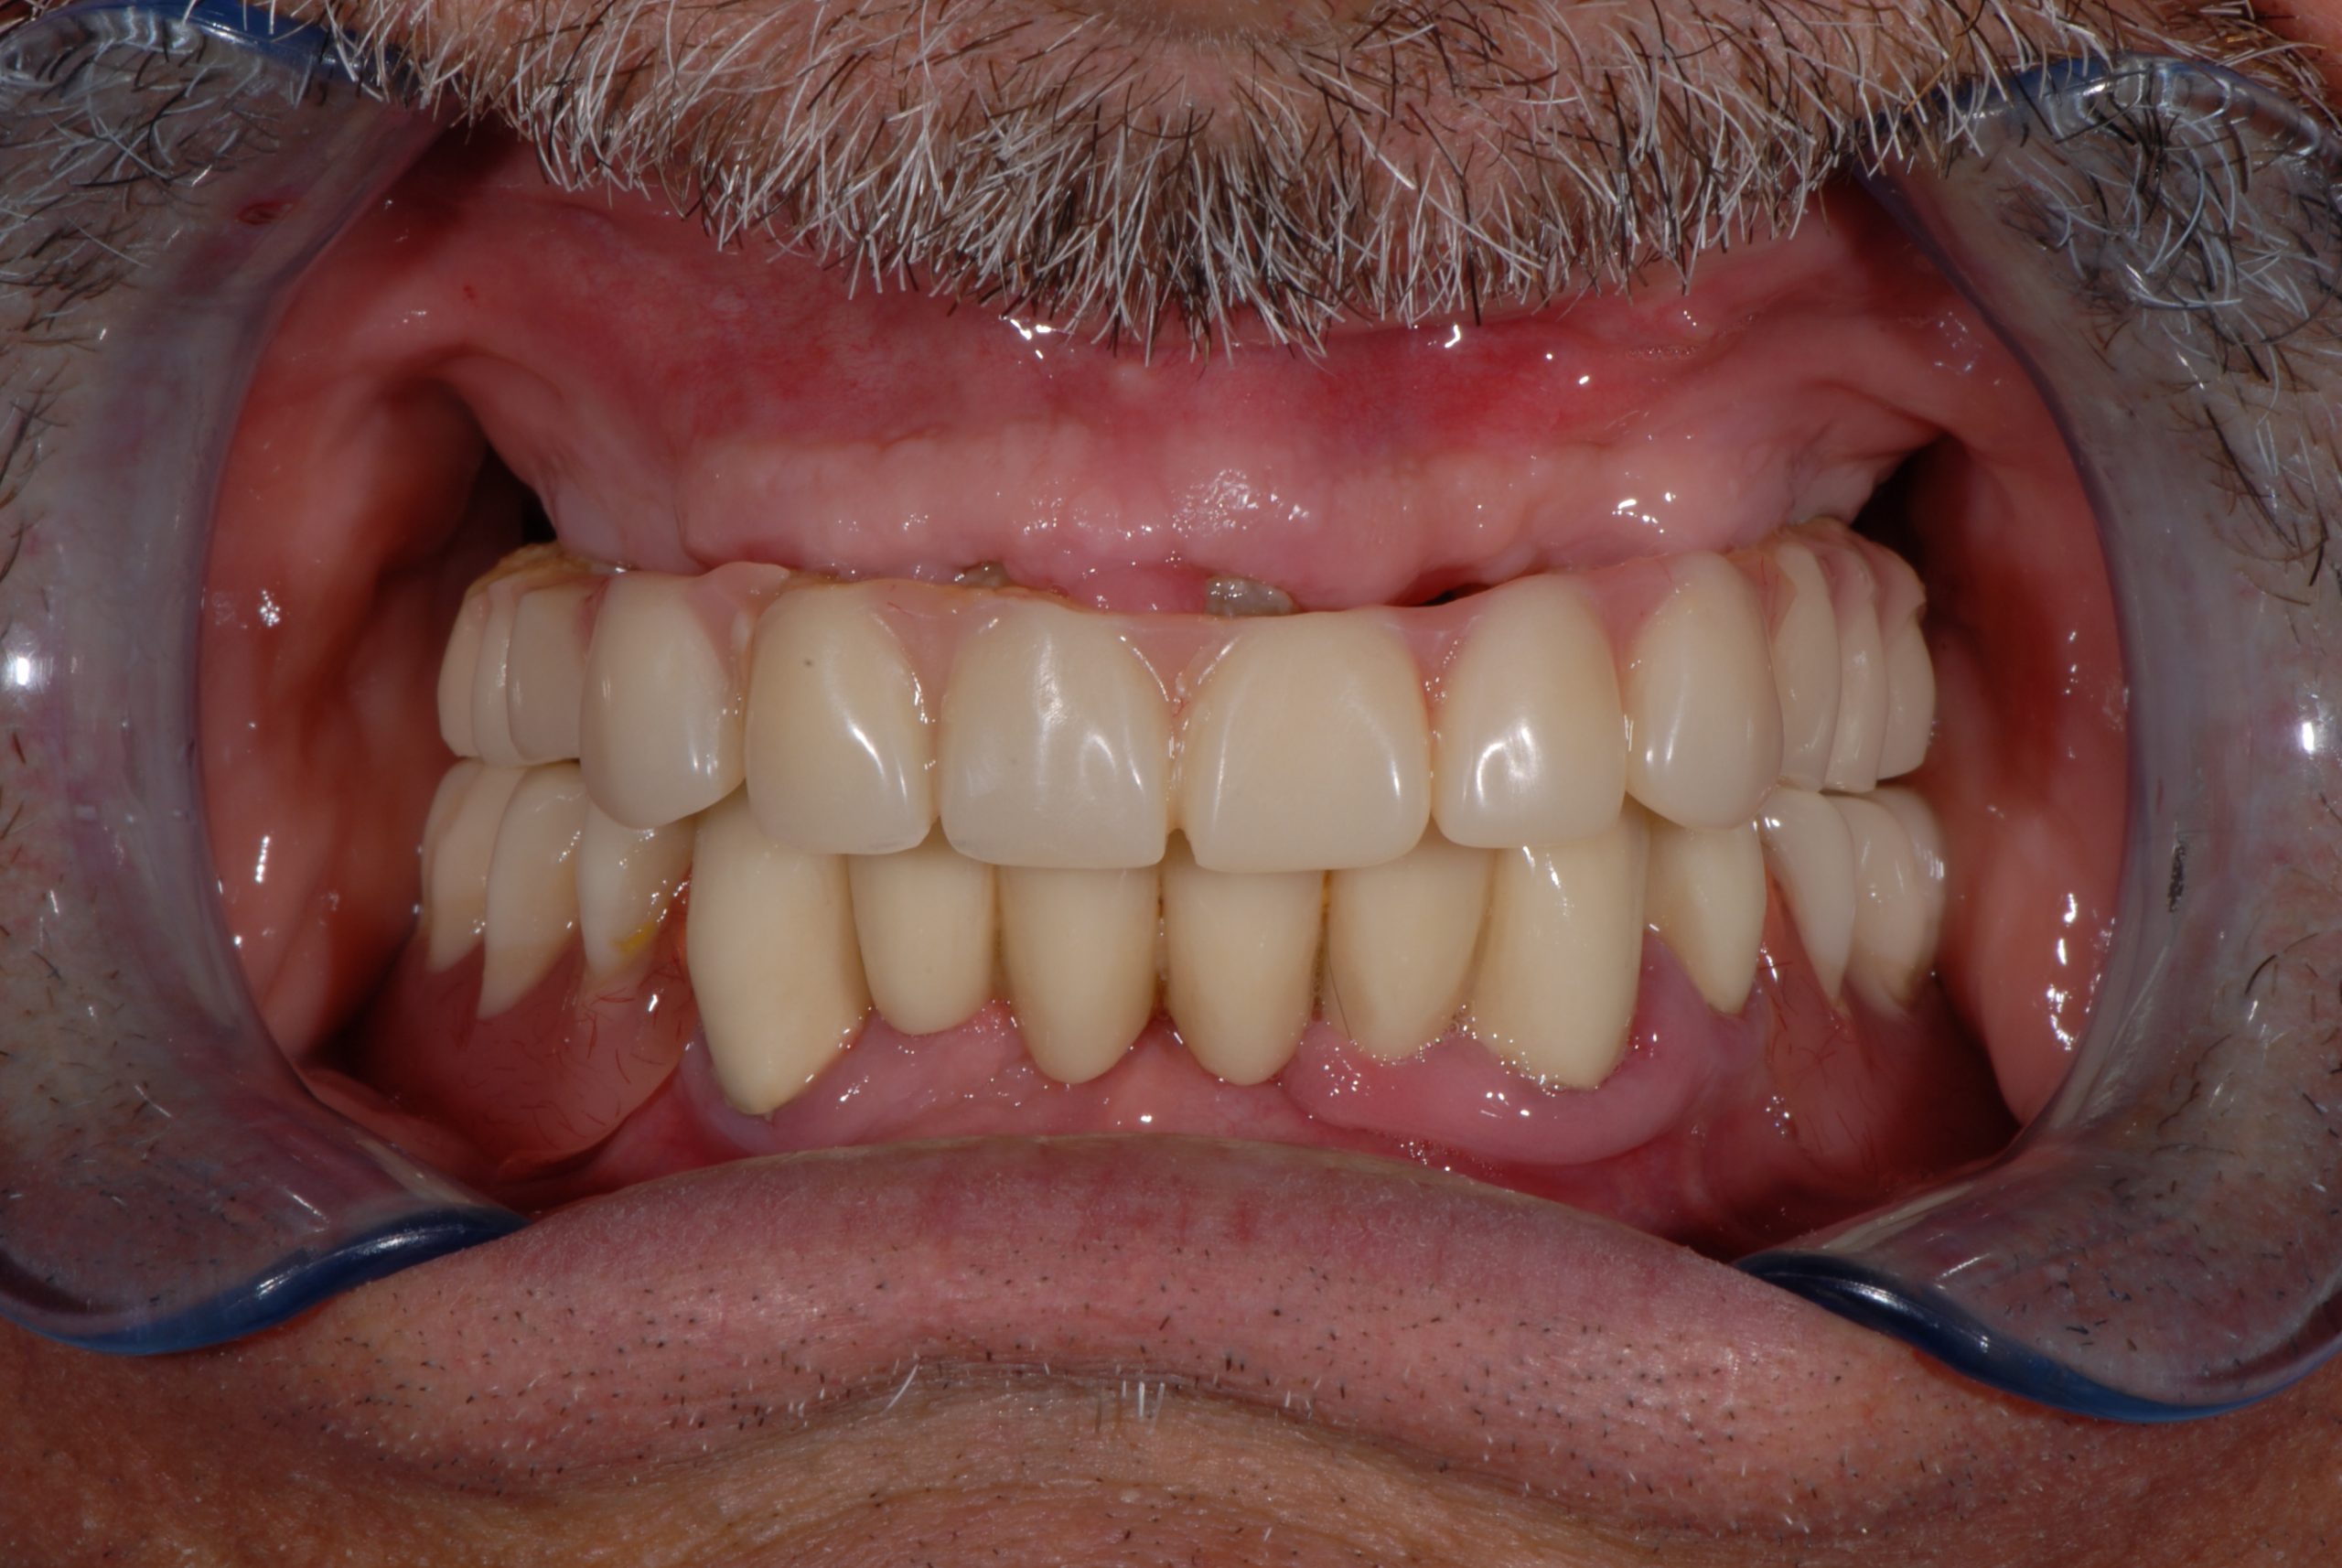

Total upper and lower rehabilitation in zirconia on implants with titanium reinforcement bars

Upper and lower prosthetic rehabilitation with titanium bars and translucent zirconia-ceramic structures. The CDP as an aid in communication between the entire team and the patient, who is the focus of the work.